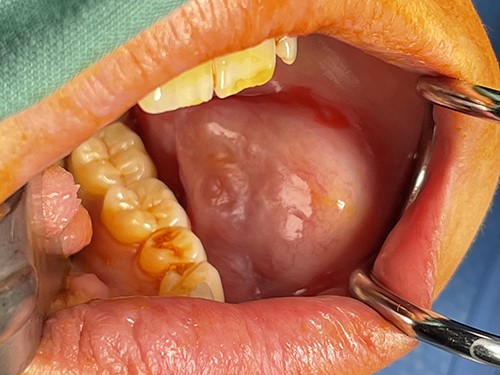

The surgeon performed an intraoral excision of the lesion under general anaesthetic (Fig. 2). It was well circumscribed and confined within the buccal soft tissues. The lesion was removed intact and primary mucosal closure achieved.

Appearance of lesion following buccal sulcus incision and dissection.